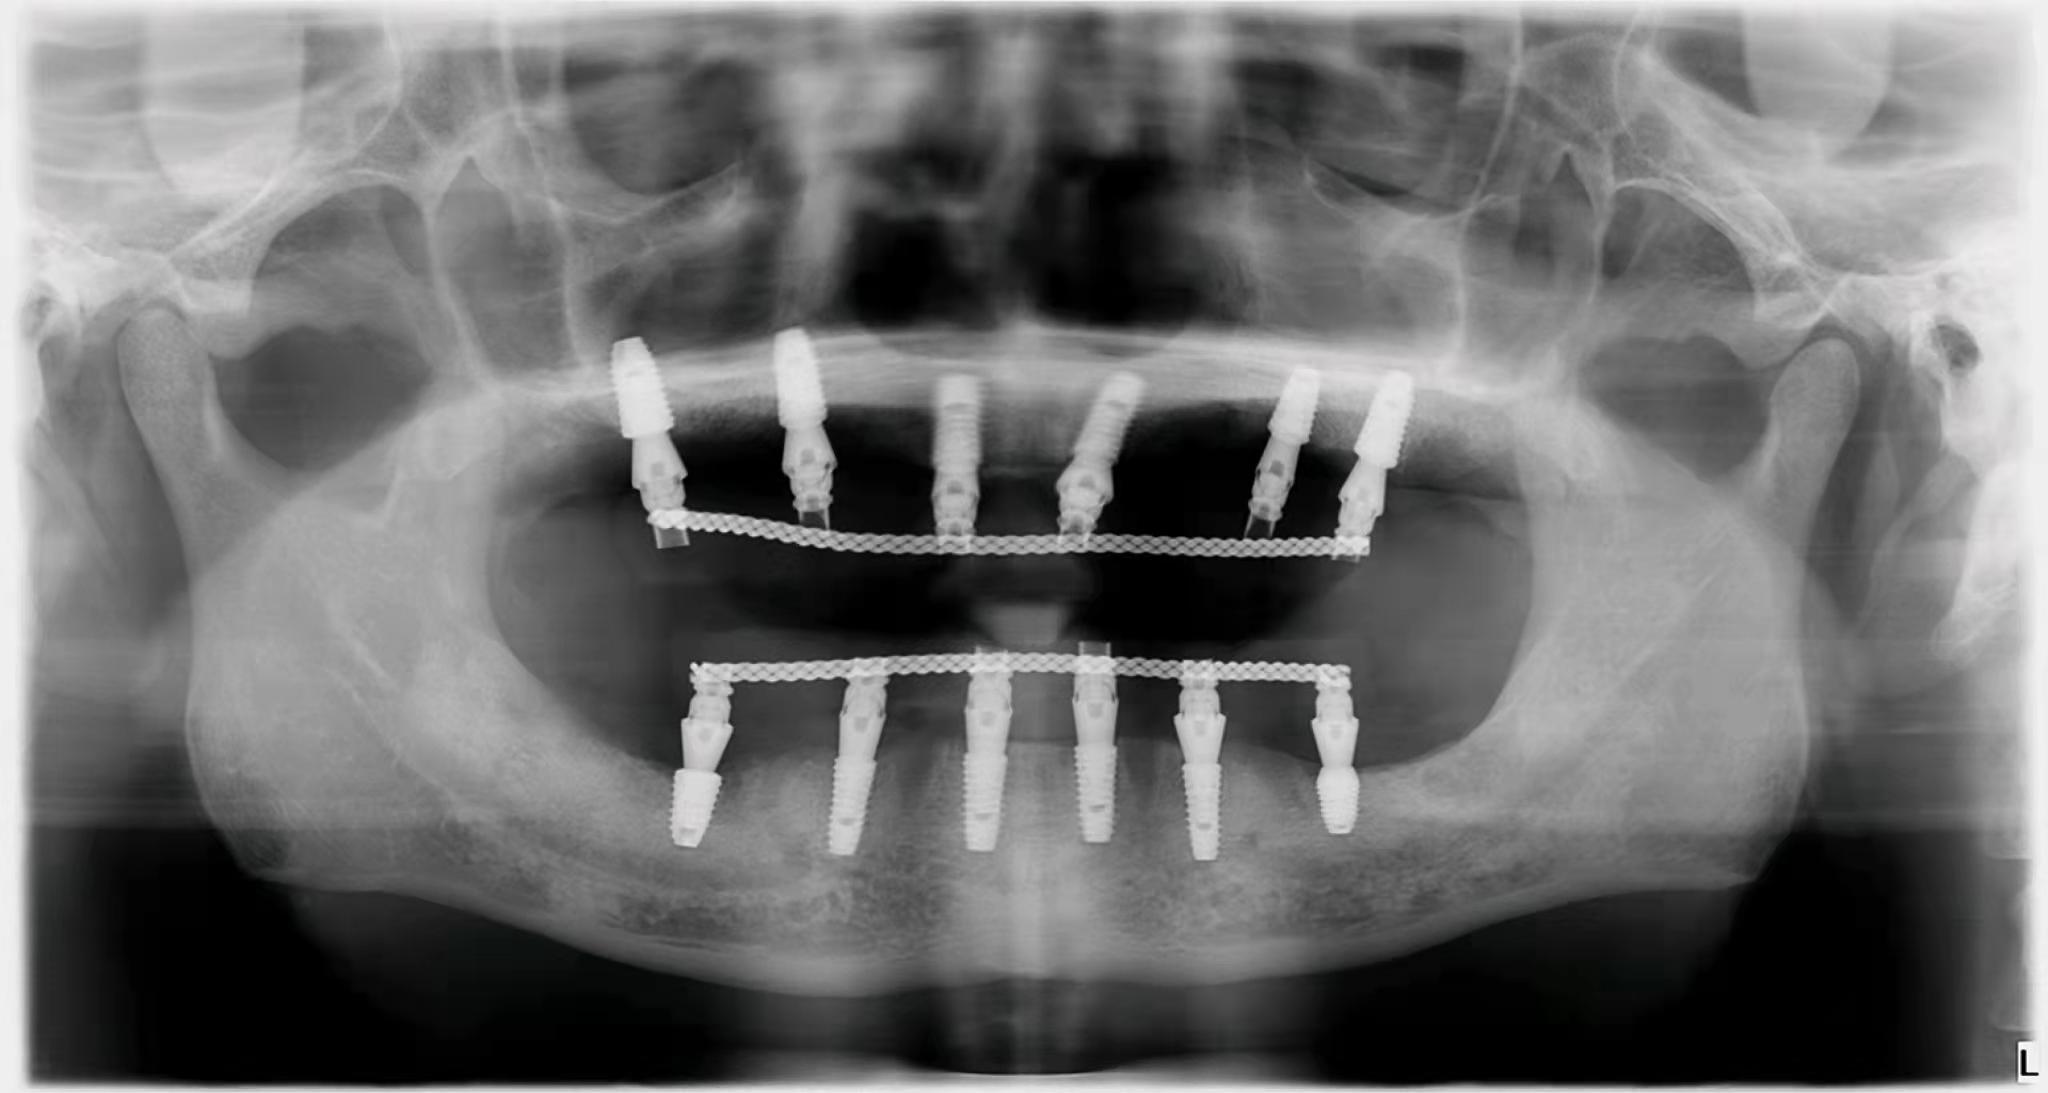

在公立和私立口腔中,與種植體不同的是,國(guó)內(nèi)部分牙冠品牌已經(jīng)被大眾接受。如果是單顆牙缺失,預(yù)算有限,可以找醫(yī)生咨詢(xún)低成本方案。即使是全口或者半口牙缺失,需要種植,也不需要在牙窩上全部種植,可以用all-one-4,或者all-one-6。